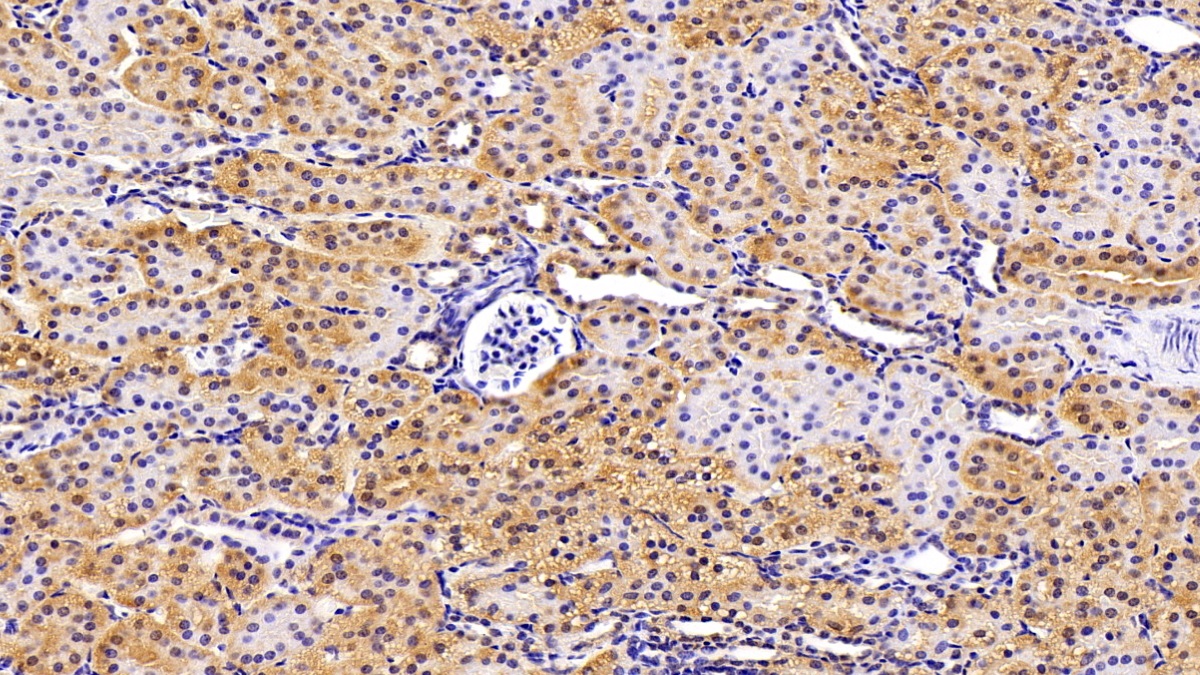

Использование высококачественных первичных антител является неотъемлемым условием получения точных и воспроизводимых результатов в современных научных исследованиях. Например, в рамках онкологического исследования удалось достоверно идентифицировать экспрессию белка PD-L1, что сыграло ключевую роль в оценке потенциальной эффективности иммунотерапии. Применение надежных антител обеспечило стабильность сигнала и высокую специфичность детекции, что позволило получить данные, пригодные для публикации в рецензируемых научных изданиях.

Способы применения первичных антител

Первичные антитела используют в разных методах: от вестерн-блоттинга до иммунофлюоресценции и проточной цитометрии. Всё решает подготовка: нужно грамотно выбрать буфер, точно рассчитать, сколько продукта добавить, и не затянуть с инкубацией. Например, в вестерн-блоттинге без правильной блокировки мембраны фон может всё испортить, а в иммунофлюоресценции фиксация клеток решает, будет ли сигнал ярким. Мы не просто продаём реагенты, а помогаем довести эксперимент до результата: подбираем реагенты и даём советы по методам, если есть специфика в протоколах производителя. Нужен особый подход? Оформите спецзаказ по ссылке — мы найдём решение для вашего проекта.